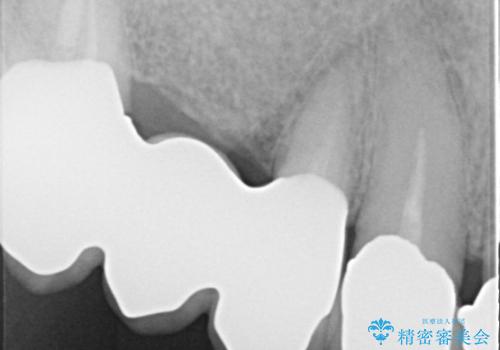

下顎の両側の奥歯が欠損しており、入れ歯をお持ちでしたが、うまく咬めずにほとんど使用していない状態でした。

上顎は全体的にクラウンの入れ替えと、下顎はインプラントの提案もしましたが、希望されなかったのでノンクラスプデンチャーの製作をする治療計画としました。

奥歯が欠損しており、上下の前歯が強く咬合する可能性があったので、上顎前歯の裏側は金属のものにしました。

お忙しい方でしたので、治療が終了するまでにじかんがかかってしまいましたが、奥歯でもしっかり咬めるようになったと喜んでいただけました。